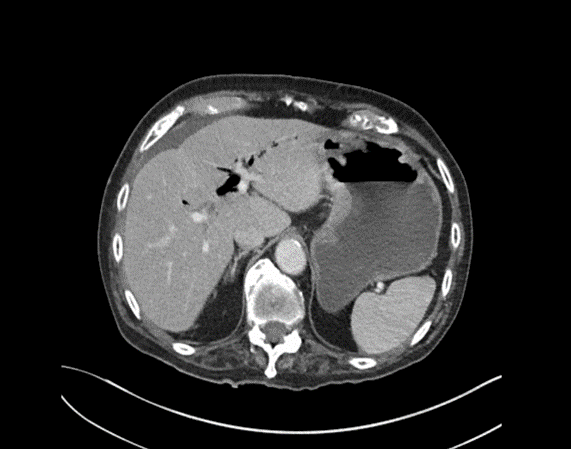

CASE 3 – A 23-year-old woman presents with 3 weeks of right upper quadrant (RUQ) pain associated with early satiety. The patient has no significant past medical history. She was born in Iraq and migrated to Australia from Syria 2 years prior to presentation. Preliminary blood results demonstrate moderate liver function test (LFT) derangement.

EXPLANATION -The case demonstrates classical appearance of a hepatic hydatid cyst. There is a well-defined rounded lesion in right lobe of liver with multiple small daughter cysts within. The fluid in the cysts can be of variable density depending on the proteinaceous contents (more protein = more dense). The thick internal septae can give a “spoke wheel” appearance as in this case. Curvilinear calcifications represents the inactive stage of the disease.

Hydatid diseases a parasitic zoonosis, caused by the larval stages of the Echinococcus granulosus .

- E. granulosusis found worldwide, however the highest rates of infection are seen in the Mediterranean and Middle Eastern regions, North Africa and South America.

- Hydatid cyst can occur anywhere in the body, the most commonly affected organ is the liver (76% of cases), followed by lung (15%) and spleen (5%).

- Classically there is a large ‘parent cyst’ which contains numerus peripheral ‘daughter cysts’.

- Humans are infected by eating the eggs of the tapeworm E. granulosus, by either eating contaminated food or through contact with dogs.

- The ingested embryos invade the intestinal mucosal wall, enter the portal circulation and develop cysts in the liver.

- Treatment options ; Surgical excision, PAIR (Puncture, Aspiration, Injection of protoscolicidal agent and Re-aspiration), Anti-helminthic agent (e.g. albendazole, mebendazole), Observation only – for inactive and silent cysts